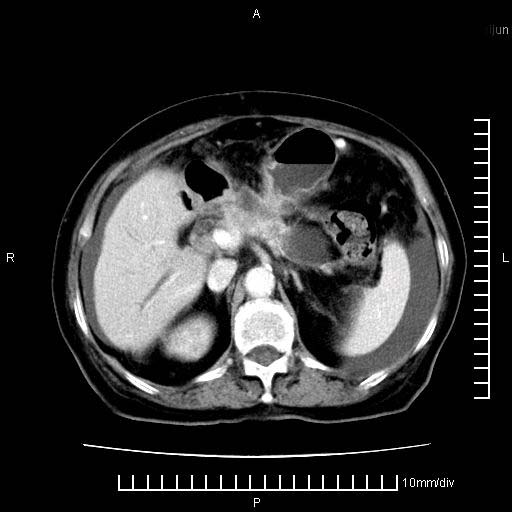

标题: CT28280:腹部增强:女性,80岁

上腹疼痛月余,外院核磁诊断胰腺癌。现临床示右下腹可明显触及包块,可片子上怎么没有看到?

1.胰腺颈体部癌。

2。腹腔积液。

3。右胸腔积液,伴右肺下叶部分萎陷。

4。右肾盂囊肿。

胰腺体部癌累及周围器官,腹膜、粘连

1。胰腺ca伴腹膜腔转移

2。肝左叶低密度灶,考虑转移可能

胰腺体部癌累及周围器官,腹膜、粘连,临床摸到的可能是粘的组织

胰腺结构模糊,胰尾部见囊性包块,周围脂肪密度增高,左肾前筋膜增厚,胸水、腹水。不符合胰腺ca伴腹膜腔转移。考虑胰腺炎伴假性囊肿形成、胸腹腔积液。

右肾盂囊肿。

1)考虑胰腺癌并胰腺假性囊肿形成。2)肝内低密度灶,不排除转移。3)右肾盂积水。4)腹水。5)右侧胸腔积液并右肺下叶部分膨胀不全。